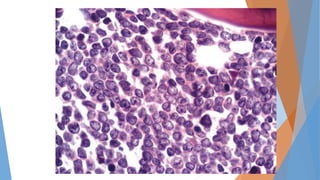

 Frote de sangre periférica

Frote de sangre periférica Normal

Las células de leucemia que se encuentran en el frotis de sangre son

característicamente linfocitos pequeños, de apariencia madura con un estrecho borde

del citoplasma y un núcleo denso que carece de discernimiento nucleolos y que tienen

cromatina parcialmente agregada.

Linfocitos atípicos o prolinfocitos, pero no debe exceder el 55%